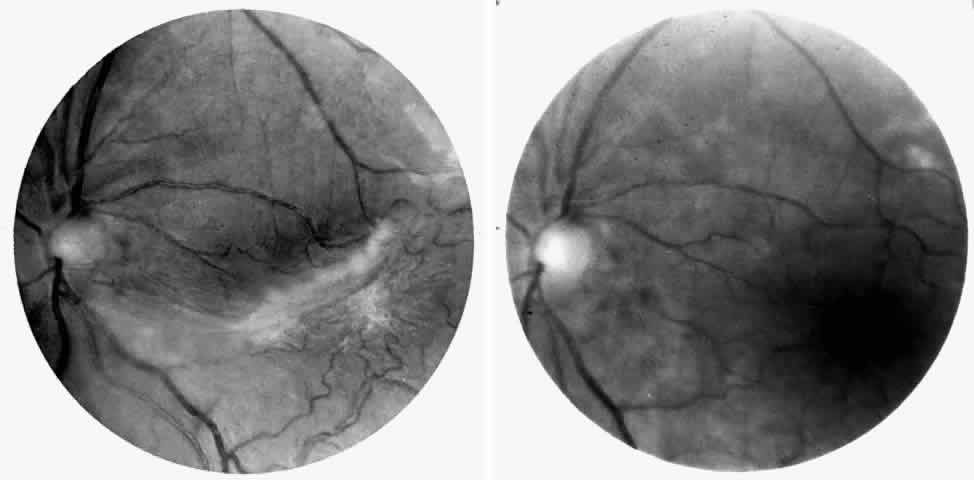

Dilation and tortuosity of the retinal veins was one of the first recognized abnormalities of sickle cell eye disease. Although it is not pathognomonic of sickle cell disease, it reportedly occurs in up to 47% of patients with homozygous sickle cell anemia and 32% of patients with SC disease (Fig. 4).70 The significance of this venous tortuosity is unknown, and the incidence does not appear to be related to age.71

Fig. 4. A. Generalized vascular tortuosity, predominantly venous, in a patient with homozygous sickle cell anemia. B. Localized macular venous tortuosity in a patient with SC disease.